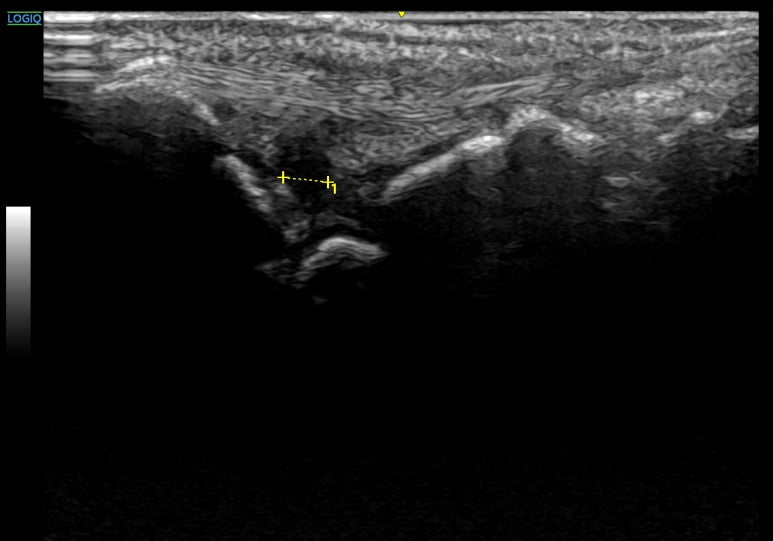

표준 검사법은 관절 조영 MRI 입니다.** * * * ## 5. 한의 진료에서 초음파가왜 중요한가요? 논문에서는 TFCC의 중심와(fovea) 부위 손상을 DRUJ(원위 요척관절) 안정성의 핵심으로 봅니다. 이 부위가 손상되면 손목이 덜렁거리는 불안정성이 생기죠. 한의학에서는 TFCC 주변의 양곡(SI5 陽谷), 양로(SI6 養老) 두 혈자리를 중요하게 보는데요.

척골 경상 돌기 부근으로, 논문에서 강조한 U(척측) 병변이 주로 발생하는 핵심 지점이고요.

척골 머리 부근으로, 손목 회전의 중심축인 DRUJ 안정성과 밀접합니다.

초음파를 통해 위 경혈들 아래의 해부학적 구조를 0.1mm 단위로 확인하고요. 염증이 있는 부위 직접 보며 시술합니다. 단순히 침을 놓는 것이 아니라, 양곡혈 초음파 영상에서 신경과 혈관 등 위험 구조물을 안전하게 피하면서 ## 목표하는 구조물에약침, 도침을 정밀하게 진입하여효과를 극대화하는거죠. 이 때 소염작용이 뛰어난 봉약침, 조직재생 효과가 뛰어난 ## PDRN 연아약침의 DNA 성분,태반약침 (자하거)**를 주로 사용합니다.